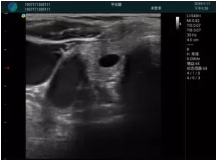

腺體內(nèi)部清晰顯示一低回聲塊影,形態(tài)不規(guī)則,邊界模糊,邊緣呈毛刺狀,內(nèi)部見砂礫樣鈣化

M20引導(dǎo)下穿刺活檢術(shù)

M20引導(dǎo)下平面內(nèi)穿刺取出的腫塊組織